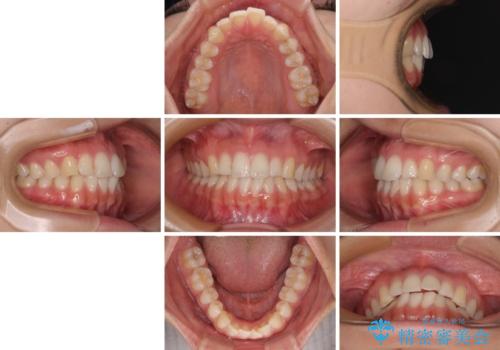

前歯の重なりをインビザライン・モデレートで矯正治療

- 上下前歯の重なりを気にして来院された患者様です。

安価なインビザラインパッケージを用いての治療を希望されており、デコボコの程度が中等度であったため、インビザライン・モデレートを用いて矯正治療を行うこととしました。

- インビザライン・モデレート

- 1年2ヶ月